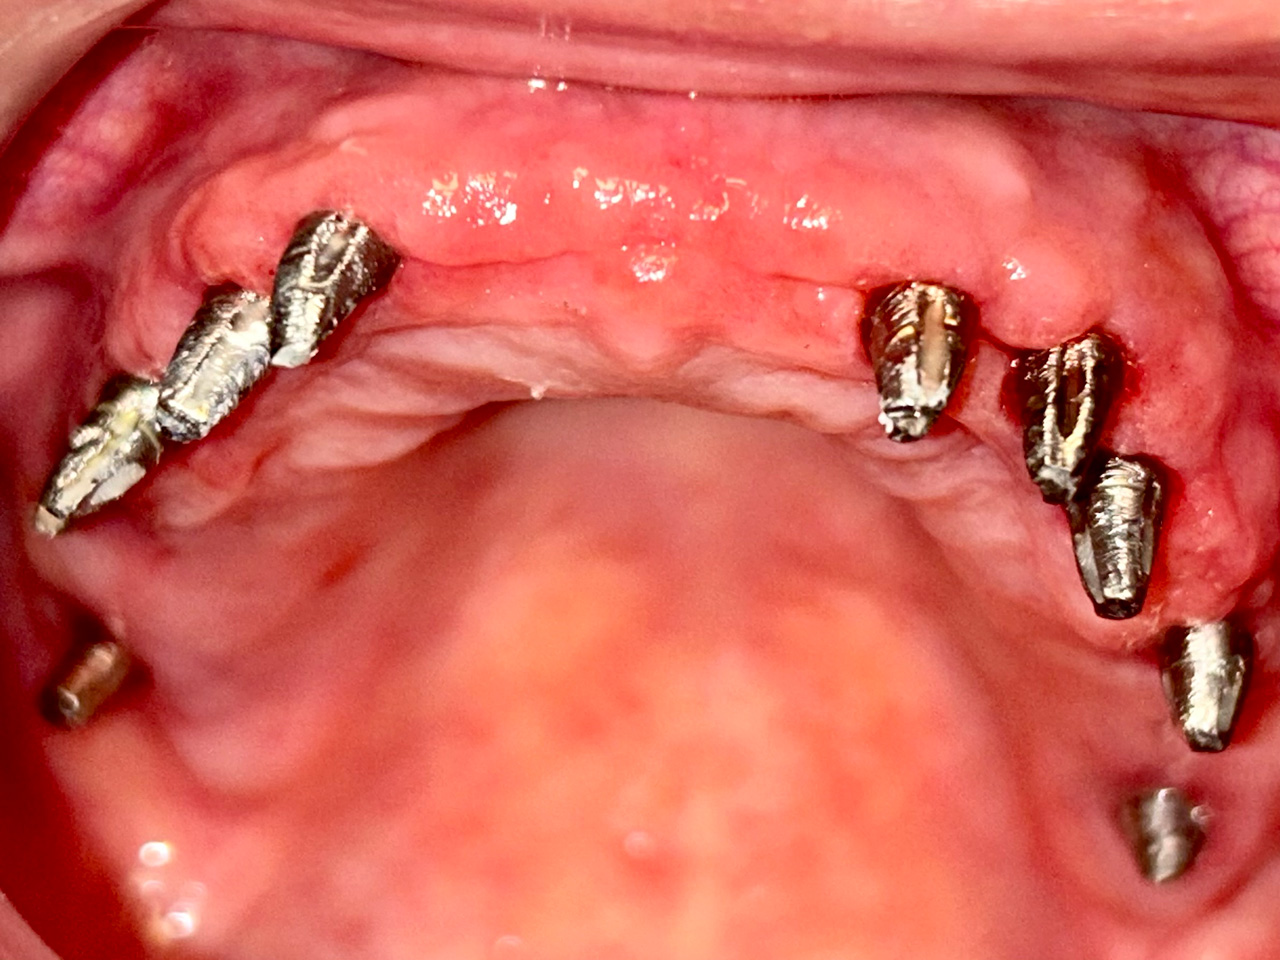

Foghiányos, fertőző gyökerekkel teli szájüreg helyreállítása

Foghiányos, fertőző gyökerekkel teli szájüreg helyreállítása esztétikailag és funkcionálisan 9 nap alatt.

A rossz fogakat és gyökereket eltávolítottuk, és azonnal terhelhető IHDE svájci implantátumokkal pótoltuk.

Az esztétikus koronák cirkóniumból készültek, hogy természetesebb hatást érjünk el